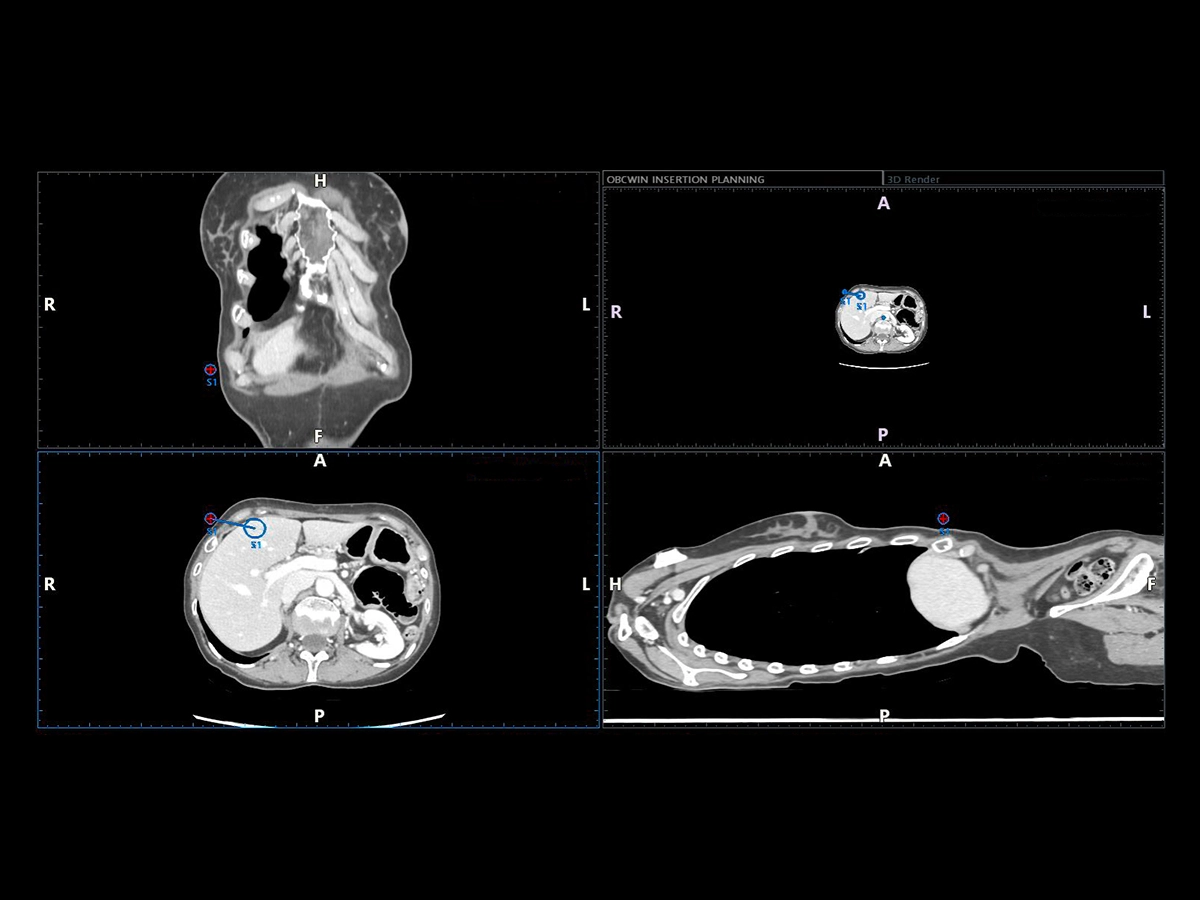

Virtual Navigator (VNav), as the most advanced Esaote Fusion Imaging technology supported by Artificial Intelligence, is opening new horizons in cross-modality liver imaging. Virtual Navigator provides a very simple and active coupling of ultrasound examination with a second Dicom modality imaging (MRI/CT/Pet-CT) dataset as a reference. It enables real-time navigation to benefit from both modalities to increase confidence and accuracy throughout interventional procedures on the liver.

Virtual Navigator will bring you particular support when you face complicated liver pathologies or conditions during your procedures, particularly in the following cases:

• Lesions which are better identified with CT, MRI, and PET or slightly visible in US

• Lesions which are only visible during arterial phase enhancement

• Composite ablations requiring multiple needle insertions.

• Complex geometries or difficult treatment planes to identify a safe pathway to the target, such as a difficult US “window”, or complex angle of insertion.

Virtual Navigator, supported by A.I., simplifies abdominal fusion thanks to the exclusive AutoSync function that enables automatic registration based on 3D camera technology. As a historical expert in fusion imaging, Esaote offers you a comprehensive package of tools to significantly reduce the complexity of interventional procedures and increase confidence in the information obtained with your ultrasound device.

• Advanced planning software